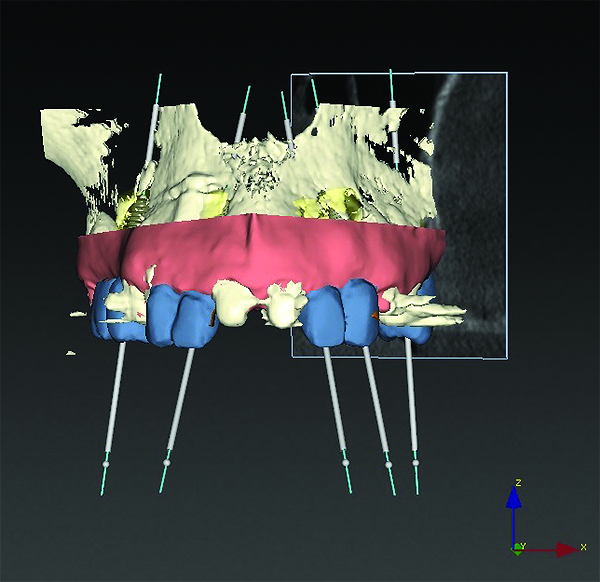

3D radiographic files (CT, CBCT) are stored digitally using a standardized digital imaging and communication in medicine (DICOM) format. In combination with a radiographic guide fabricated from a diagnostic wax-up, CBCT can be used to plan implant location and angulation based on prosthetically driven parameters and local bone/tissue constraints (Figure 8 through Figure 11). Currently, there are two different protocols to incorporate the radiographic guide in 3D scans and to perform computer guided surgery. The first is the double scan protocol, in which the patient wearing the radiographic guide and the radiographic guide alone are scanned separately. Fiduciary markers incorporated in the radiographic guide allow for matching of the two scans. This protocol allows for digitization of the surgical guide with great accuracy, irrespective of errors introduced by patient scans.18 Specialized software can be used to create a surgical guide (Figure 12).

3D radiographic scans obtained using the single scan protocol can be combined with digital mock-ups performed on intraoral optical scans or scans of casts,20 using the existing natural teeth as fiduciary markers. Different masks for bone, teeth, gingiva, and implants can be designated and processed (Figure 13 and Figure 14). This technology allows for greater accuracy, since implant position will be determined based on natural teeth (fiduciary markers) that are likely to be more stable and accurate than fiduciary markers placed on a radiographic guide.

(8) The use of CBCT and digital software for implant treatment planning. The radiographic guide in combination with a 3D CBCT was used to help plan implant position and location.

Figure 8

(9) The use of CBCT and digital software for implant treatment planning. The radiographic guide in combination with a 3D CBCT was used to help plan implant position and location.

Figure 9

(10) The use of CBCT and digital software for implant treatment planning. The radiographic guide in combination with a 3D CBCT was used to help plan implant position and location.

Figure 10

(11) The use of CBCT and digital software for implant treatment planning. The radiographic guide in combination with a 3D CBCT was used to help plan implant position and location.

Figure 11

(13) An optical scan of patient’s teeth and diagnostic wax-up was combined with CBCT to facilitate treatment planning of implant placement. Note that there is a need for sinus augmentation to accommodate a dental implant on the right image (blue: tooth contours determined from wax-up/optical impression, red: soft tissue outline).

Figure 13

(14) An optical scan of patient’s teeth and diagnostic wax-up was combined with CBCT to facilitate treatment planning of implant placement. Note that there is a need for sinus augmentation to accommodate a dental implant on the right image (blue: tooth contours determined from wax-up/optical impression, red: soft tissue outline).

Figure 14